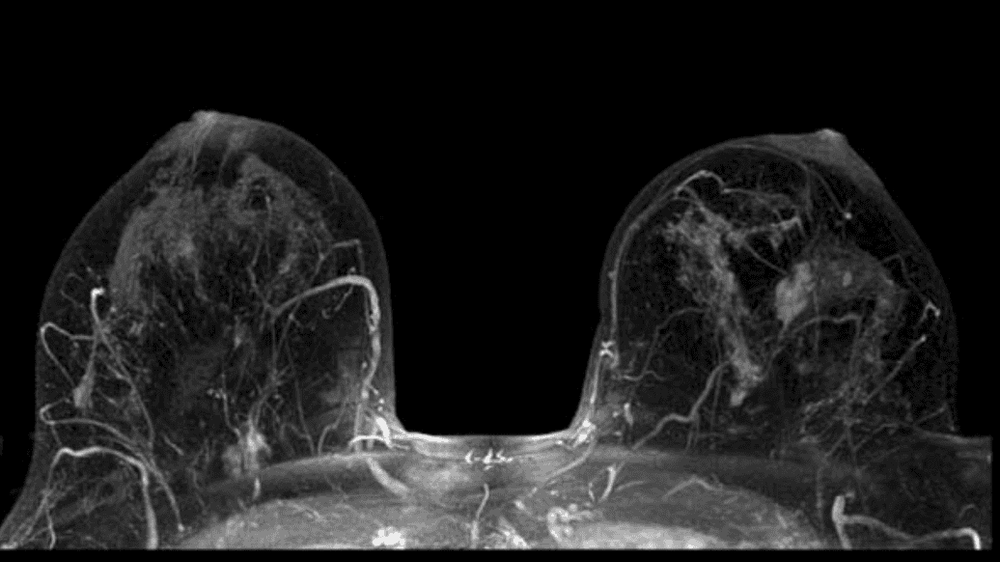

3.5 MRI của vú

MRI có thể được sử dụng với chụp nhũ ảnh để phát hiện ung thư vú, đặc biệt ở những phụ nữ có mô vú dày đặc hoặc những người có nguy cơ mắc bệnh cao.

Kết quả chụp MRI vú giúp phát hiện ung thư vú